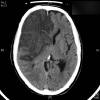

AVC amplio de territorio de A. cerebral media